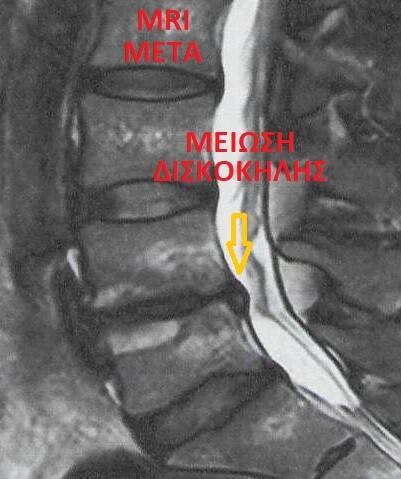

Μείωση δισκοκήλης μετά από έγχυση ενδοδισκικής γέλης (gel) ABSOLUTE GEL Ο4-Ο5 (ΔΕ)

Έλεγχος με MRI 12 μήνες και 28 ημέρες μετά την επέμβαση

Βελτίωση ασθενούς 85%

Ασθενής Σ.Ε. 40 ετών (θήλυ) με δεξιά ισχιαλγία

Ημερομηνία επέμβασης 09/09/2024

MRI μετά την επέμβαση